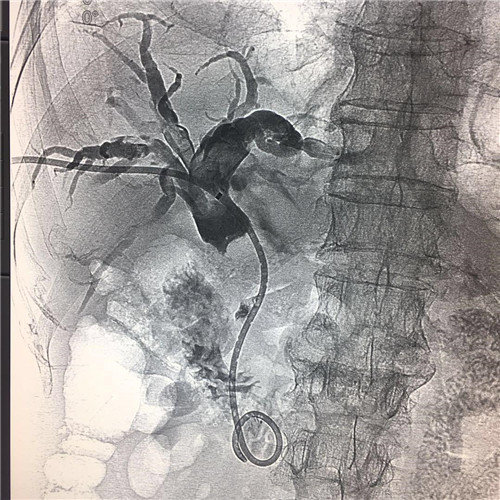

4月4日,乐鱼在线登录入口介入科成功为一位78岁高龄,胆系高位梗阻性黄疸、胆管占位病变的患者紧急成功实施了PTCD(经皮肝穿胆管引流术)。

患者全身皮肤金黄瘙痒难忍,在B超定位下行肝内胆管引流术、术后因引流不畅拔管;在胃镜下逆行ERCP胆管支架植入术,经过术者反复操作,但导丝无法通过病变段。看到患者痛苦不堪,家属迫切治疗的场面,介入科李建国主任现场会诊提出为患者在介入下行PTCD治疗的意见。术前经过讨论制定多套严密方案,与患者及家属多方沟通达成介入手术共识;术中精准定位穿刺选择不同的导丝、导管多角度旋转闭塞原地不动,时间一分一分过去......在医护人员努力下,闭塞的胆道开通了,再经球囊分段扩张病变狭窄段,内外引流管放置顺利300余毫升的黑褐色胆汁流出......

在护理人员精心的配合下,手术历时30余分钟圆满成功,彻底解决了患者梗阻性黄疸引发的皮肤黄染,保护了肝功能。

顺行开通高位胆管梗阻性黄胆经皮肝穿胆管引流术优势明显